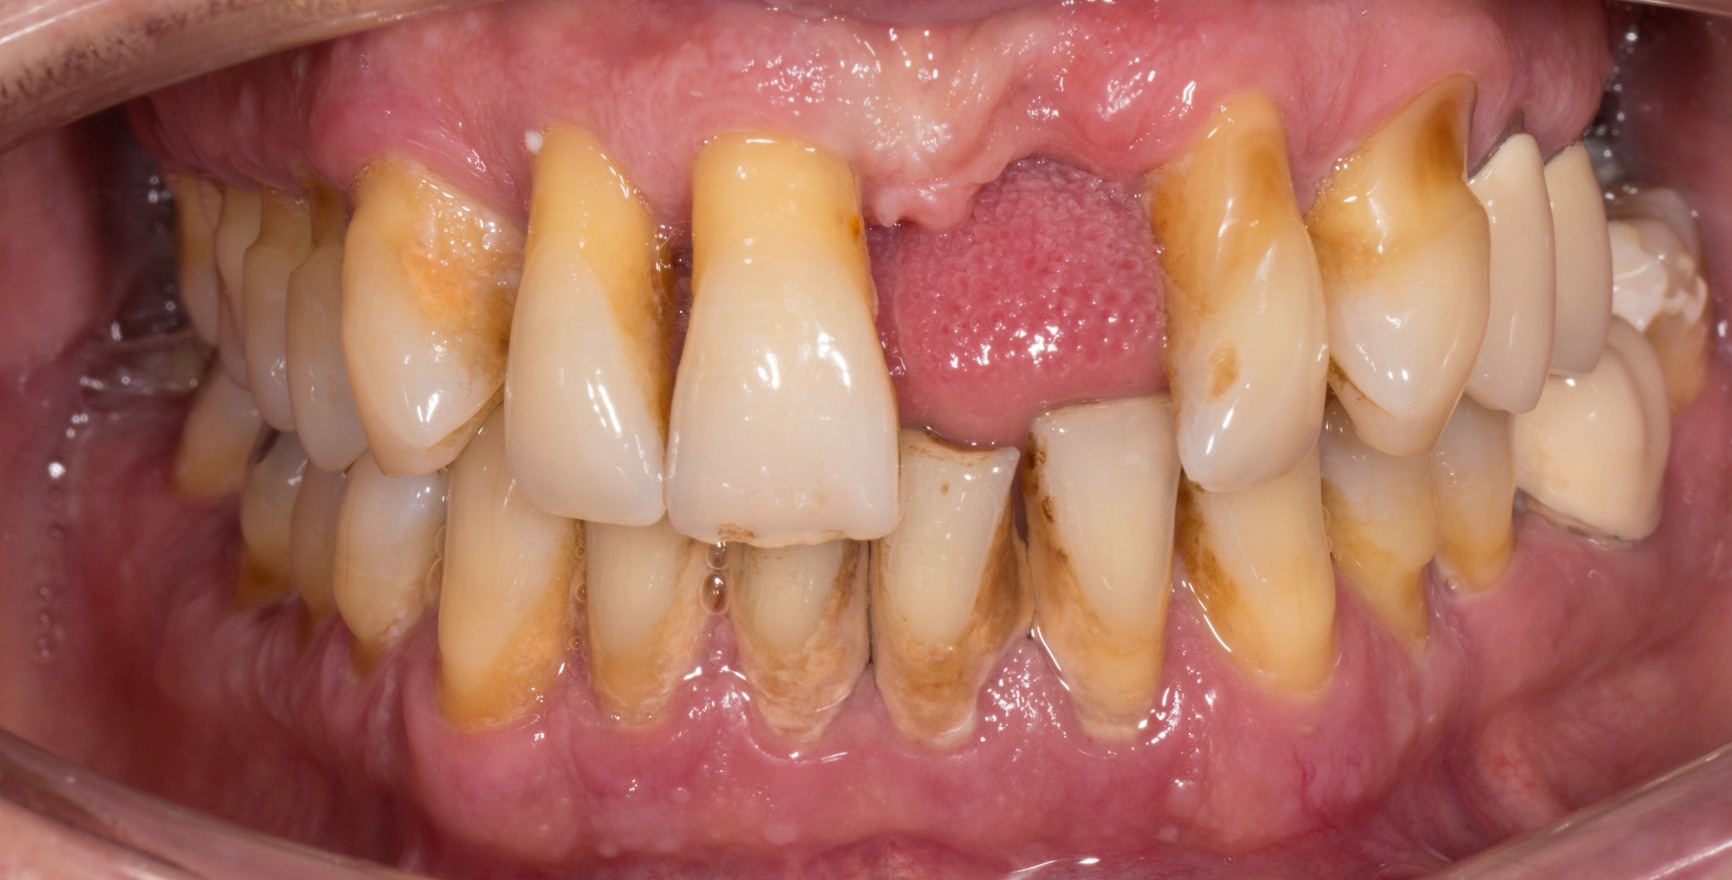

For the first time, the new classification scheme for periodontal diseases, which was presented in June 2018, contains a definition of the concept of clinical periodontal health (Lang & Bartold, 2018). Even under optimum hygiene conditions, a small quantity of bacterial biofilm is present in the gingival sulcus. A complete absence of bacteria is not possible under clinical conditions. The histological response to this is a limited subepithelial infiltrate of neutrophilic granulocytes (PMN). However, providing homeostasis is maintained between the biofilm and a small quantity of PMN infiltrate, this state is seen as an expression of immunological control and thus as a physiological process, not a pathological (inflammatory) one (Brecx et al., 1987a+b). The microbiological load and host factors determine whether the state of clinical periodontal health continues. Locally, these can lead to an increased accumulation of biofilm (e.g. inadequate dental restorations or unfavourable tooth positions) or they can affect the immune response (e.g. systemic diseases).

A state of clinical periodontal health in the intact periodontium is distinguished from that in a reduced periodontium already affected by clinical loss of attachment. This loss of attachment can occur:

as result of inflammation during the course of periodontitis. Clinical periodontal health then describes a stable condition after successful completion of periodontal treatment.

The clinical criterion is always the absence of bleeding on careful probing (bleeding on probing = BoP). A distinction is made between a site/tooth-specific diagnosis with a negative BoP finding at the corresponding measurement site, and diagnosis on the level of the tooth or patient, for which a threshold value of a BoP ≤ 10% still meets the criteria of clinical periodontal health. Pocket probing depths must be no more than 3 mm. In a reduced periodontium after periodontal treatment, a threshold value of 4 mm is still regarded as a stable status (Matuliene et al., 2008).